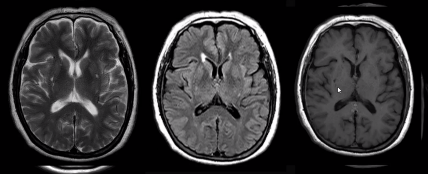

如下图所示,脑梗死的发病部位符合动脉血管分布区:

1.脑梗死影像学表现及分期

(1)超急性期(<6h):CT 及 MRI 检查阴性,DWI 呈明显高信号。

(2)急性期(6-72h):CT 表现低密度区,MR 表现长 T1 长 T2 异常信号,DWI 呈较明显高信号。

(3)亚急性期(72h-10d):CT 表现同时累及灰白质的楔形或三角形低密度区,MR 可伴出血, DWI 呈明显高信号,占位效应显著,增强扫描可见强化。

(4)慢性期(&11d):脑软化,脑萎缩。